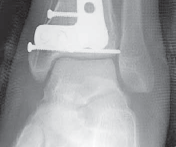

62.

An anterior plate location is often best for neutralization or buttressing of complex intra-articular fractures. TECH FIG 5 • A,B. Lag screws are used and anterior plating is performed to optimize fixation of the articular segment with a raft of anterior–posterior screws. Autograft from the tubercle of Gerdy was used above the disimpacted articular surface, but allograft or substi- A B tutes may be used.

TECH FIG 5

(continued)

• C,D. Radiographs show appearance immediately postopera- C D tively. #### WOUND CLOSURE AND CARE